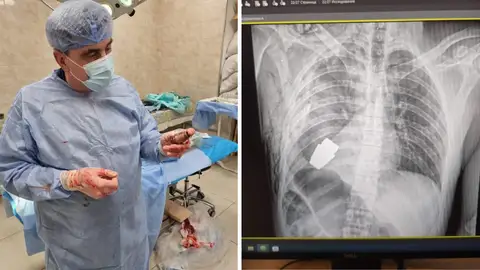

Un grupo de cirujanos ha logrado extraer del pecho de un soldado ucraniano una granada. Así lo han dado a conocer las Fuerzas Armadas del país esta semana, cuando la intervención quirúrgica se producía "exitosamente".

Ha sido el mayor general Andrii Verba, un experimentado cirujano militar, el que ha logrado extraer con éxito el artefacto explosivo al no hacer uso de la electrocoagulación. A pesar de ello, el personal sanitario se temía lo peor, pues "la granada podía detonar en cualquier momento".

En el interior de la sala se encontraban dos zapadores que, tal y como ha explicado el gobernador regional, "vigilaban la seguridad del personal médico y del paciente".

"Nuestros médicos militares realizaron una operación para extraer una granada sin explotar del cuerpo de un militar. Uno de ellos, el más experimentado de las Fuerzas Armadas, el mayor general Andriy Verba, trabajó sin electrocoagulación, ya que la granada podía detonar en cualquier momento", ha explicado Serhii Borzov, el gobernador regional, en su cuenta de Facebook, donde ha publicado una imagen de los rayos X y otra del momento de la extracción.

El impacto de la granada en el torso de este militar se produjo durante una sangrienta batalla en Barkhmut, en Ucrania. Ahora, horas después, y tal y como han subrayado las Fuerzas Médicas de las Fuerzas Armadas, el hombre se encuentra estable.